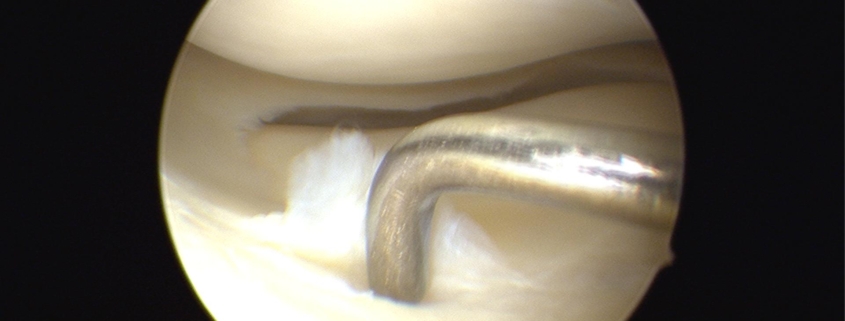

- Surgery: For more serious tears, arthroscopic surgery may be recommended. During this minimally invasive procedure, a surgeon repairs or trims the tear.